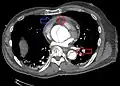

Computed tomography angiography is a fast, non-invasive test that gives an accurate three-dimensional view of the aorta. These images are produced by taking rapid, thin-cut slices of the chest and abdomen, and combining them in the computer to create cross-sectional slices. To delineate the aorta to the accuracy necessary to make the proper diagnosis, an iodinated contrast material is injected into a peripheral vein. Contrast is injected and the scan performed using a bolus tracking method. This type of scan is timed to injection to capture the contrast as it enters the aorta. The scan then follows the contrast as it flows through the vessel. It has a sensitivity of 96 to 100% and a specificity of 96 to 100%. Disadvantages include the need for iodinated contrast material and the inability to diagnose the site of the intimal tear.

Type A dissection with pericardial effusion as a result.